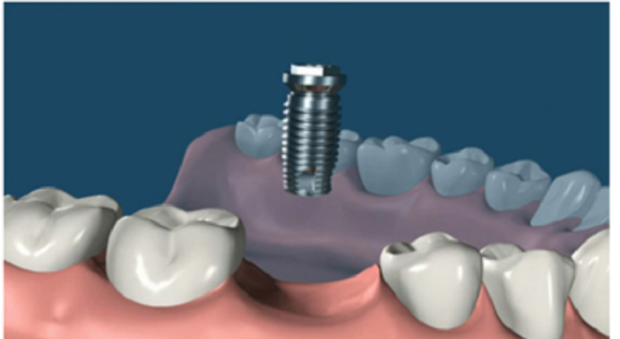

3. 植入種植體:這個(gè)時(shí)候開始進(jìn)行第一期手術(shù),手術(shù)將在牙槽骨上選擇合適的位置打洞,植入種植體后縫合創(chuàng)口,正常情況下整場(chǎng)手術(shù)時(shí)長在半個(gè)小時(shí)左右。